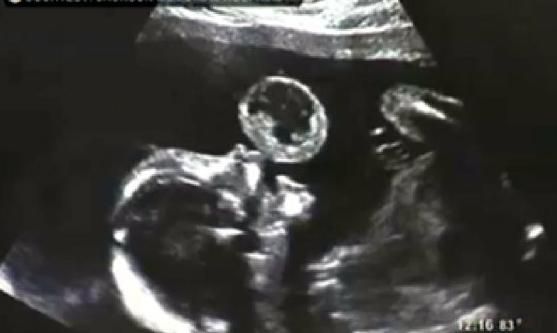

Mổ lấy u trong bào thai

Thành tựu y tế thế giới nổi bật 2012 4

Ca mổ được coi là trường hợp đầu tiên trên thế giới. Các bác sĩ đã tiến hành phẫu thuật cắt bỏ 1 khối u ở miệng cho một thai nhi mới chỉ có 17 tuần tuổi và vẫn còn ở trong bụng mẹ. Nếu không phẫu thuật, khả năng sống sót của thai nhi rất thấp. Người mẹ tên là Tammy Gonzalez được gây tê cục bộ, các bác sĩ đã lấy một chiếc kim chọc qua túi ối sau đó cắt bỏ khối u bằng tia lazer. Ca phẫu thuật đã kéo dài hơn 1 giờ và điều kỳ lạ là 5 tháng sau, em bé đã chào đời hoàn toàn khỏe mạnh. Hiện em chỉ có một vết sẹo nhỏ nơi khóe miệng. Ca mổ được tiến hành từ năm 2010, song mãi đến năm 2012 mới được công bố.